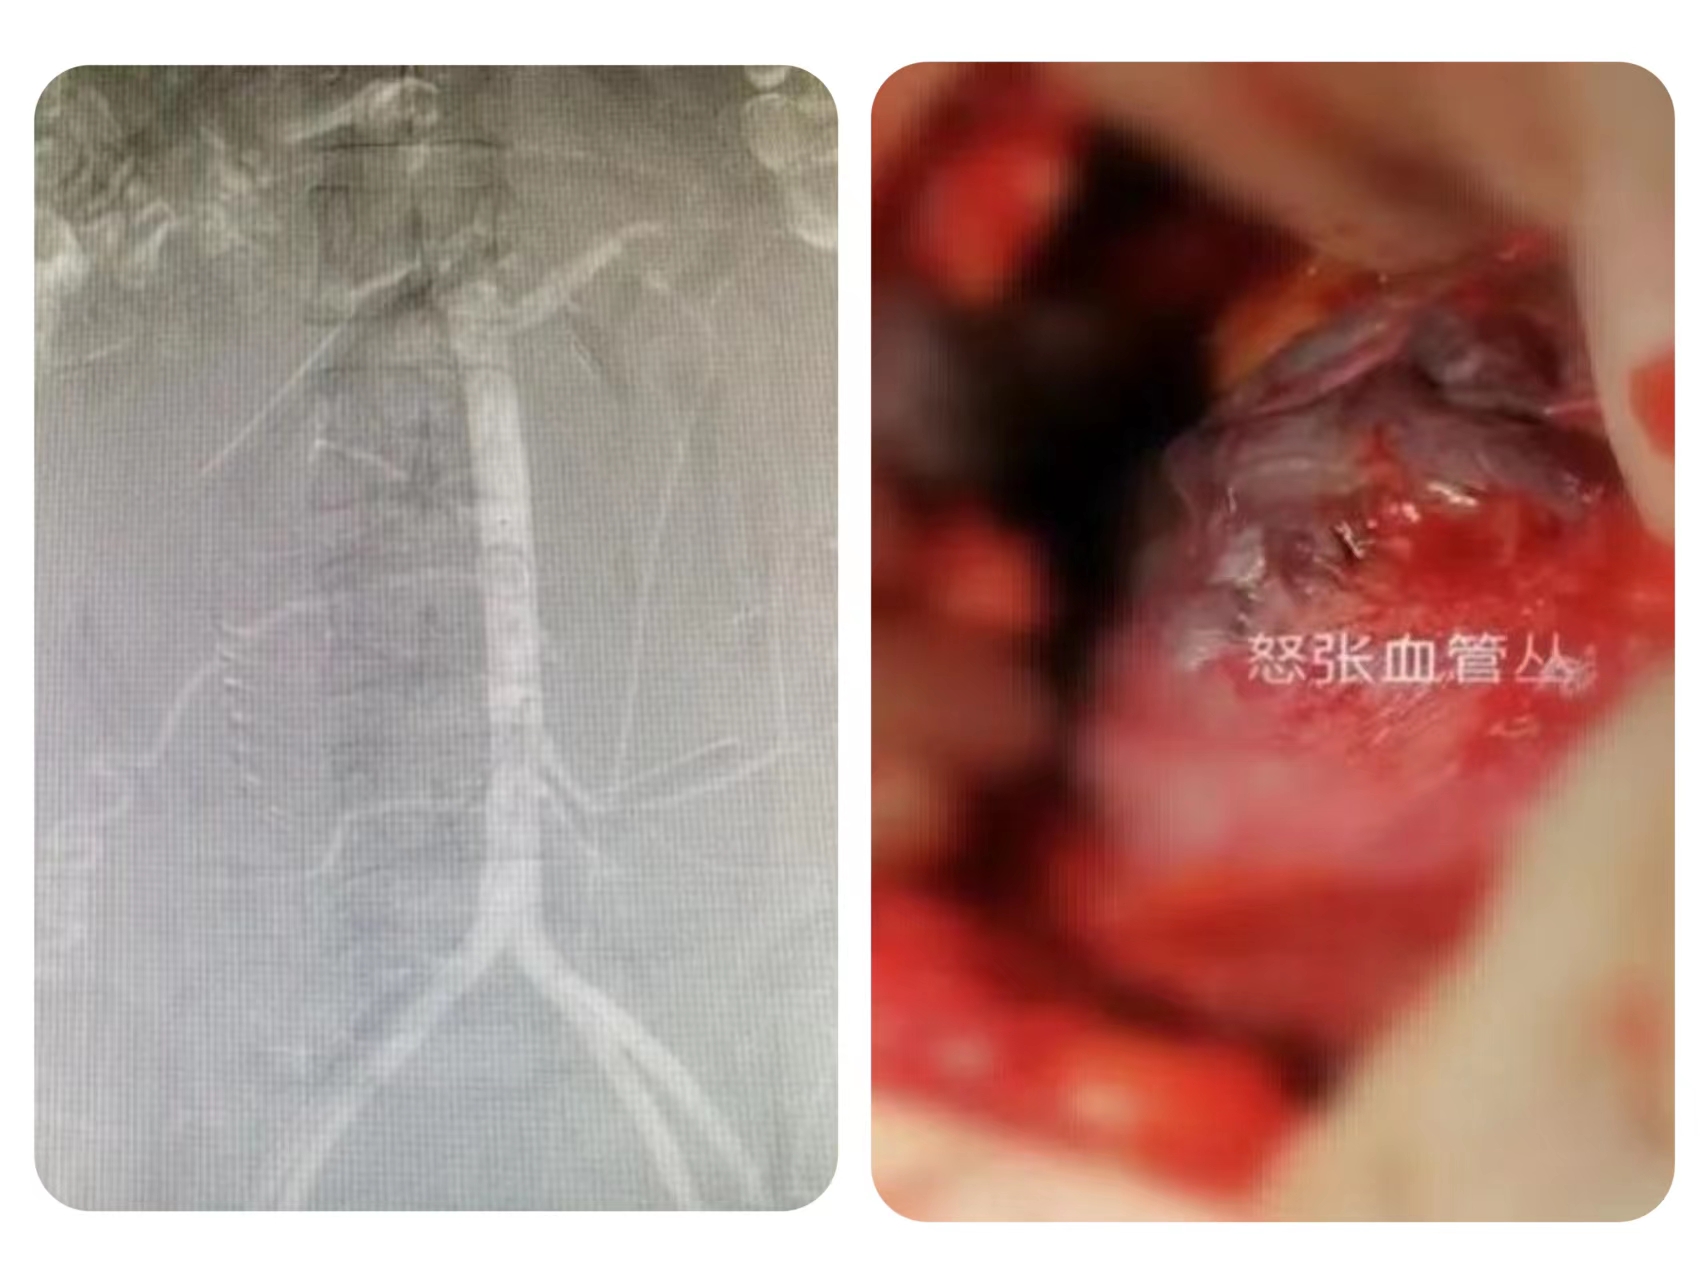

20日上午,患者顺利产下一名活男婴,子宫收缩具体,出血量约300ml,母子安全,手术成功。这是本轮疫情期间,医院多科室联动成功开展的第一例经腹主动脉造影+球囊封堵术+子宫下段剖宫产术,新生儿科和输血科为手术的成功开展,也做了充足的保障。